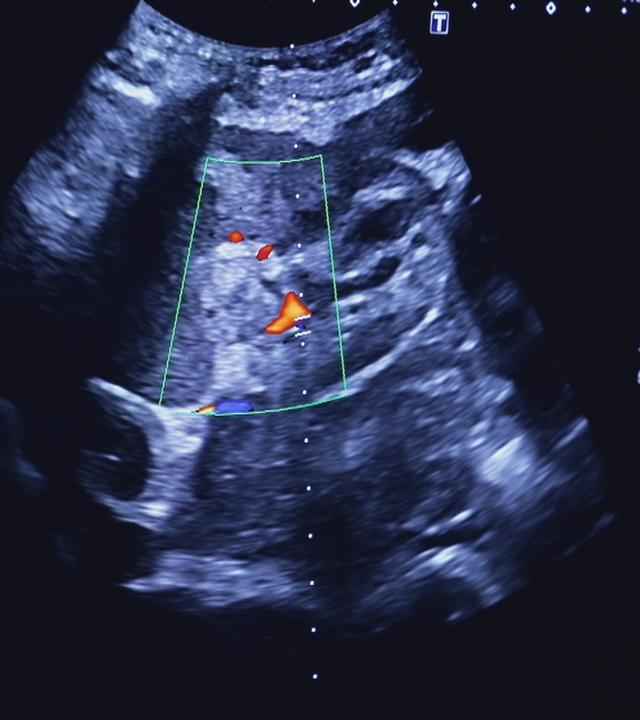

Die Nieren sind wahre Multitalente und für unser Leben unverzichtbar. Wenn sie nicht mehr funktionieren, gibt es jedoch kaum eine Lösung. Was bedeutet eine chronische Nierenerkrankung für Betroffene?